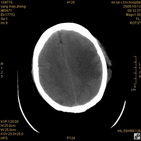

病人杨XX,男,青云街道办事处路踏泉村,住院号51666,CT号:104770。病人因“高血压脑出血”在新泰市人民医院住院治疗5天,治疗效果不佳转入我院,复查CT示左基底节血肿,病人昏迷状态,给予血肿清除术,术后2天复查CT,血肿完全清除,病人恢复好,治疗效果满意。附病人术前术后CT片资料如下。

术前CT

术前CT1 术前CT2 术前CT3 术前CT4